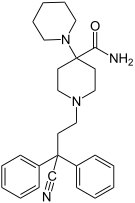

The first fully synthetic opioid was meperidine (later demerol), found serendipitously by German chemist Otto Eisleb (or Eislib) at IG Farben in 1932.[228] Meperidine was the first opiate to have a structure unrelated to morphine, but with opiate-like properties.[199] Its analgesic effects were discovered by Otto Schaumann in 1939.[228] Gustav Ehrhart and Max Bockmühl, also at IG Farben, built on the work of Eisleb and Schaumann. They developed "Hoechst 10820" (later methadone) around 1937.[230] In 1959 the Belgian physician Paul Janssen developed fentanyl, a synthetic drug with 30 to 50 times the potency of heroin.[211][231] Nearly 150 synthetic opioids are now known.[228]

Diphenylpropylamine derivatives

- Propoxyphene

- Dextropropoxyphene

- Dextromoramide

- Bezitramide

- Piritramide

- Methadone